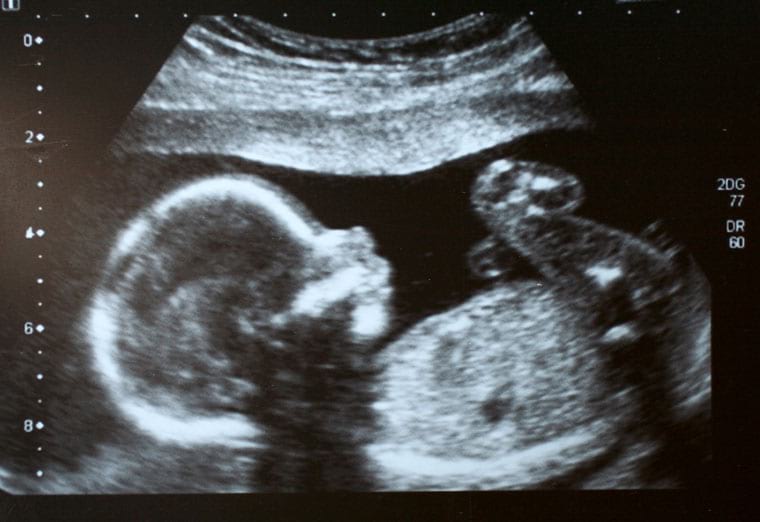

ודוק, לפני ההחלטה להיכנס להריון, עומדת לרשות בני הזוג האפשרות לבצע בדיקות סקר גנטיות, אשר ניתן לאתר באמצעותן את המוטציה בדנ"א שגורמת להיווצרות האנמיה החרמשית. כמו כן, במהלך ההריון ניתן לאתר בעובר עצמו את המוטציה הרלוונטית, באמצעות דיקור מי שפיר או בדיקת סיסי שליה (ראו מאמר: בדיקת סיסי שליה: החשיבות והסיכונים).

לא זו אף זו, בנוסף לבדיקת הדם שניתן לבצע לפני ההריון, כאמור, יכולים ההורים החפצים בכך לבצע בדיקת מי שפיר או בדיקת סיסי שליה, אשר באמצעותן ניתן לאתר את מחלת האנמיה החרמשית בעובר באופן ישיר. יחד עם זאת, בניגוד לבדיקת הדם, קיים סיכון מסוים לאישה ההריונית ולעוברה בביצוע בדיקת מי השפיר ובדיקת סיסי השליה, שכן במהלכן מוחדרת מחט ארוכה לביטנה של האישה. כך, על פי נתונים רפואיים סטטיסטיים, אחת מכל עשרים אלף נשים שעוברת את הבדיקה מתה לאחריה, בעקבות חדירתו של הנוזל השפירי למערכת הדם (תופעה הנקראת תסחיף אמניוטי). על כן מוטלת על הרופא שעורך את הבדיקה ליידע את האם אודות אותם סיבוכים ולאפשר לה להגיעה להחלטה מושכלת באשר לעריכת הבדיקה. אי יידוע האישה או מתן מידע חלקי, עשוי להקים לאישה עילת תביעת רשלנות רפואית כנגד הרופא המטפל.